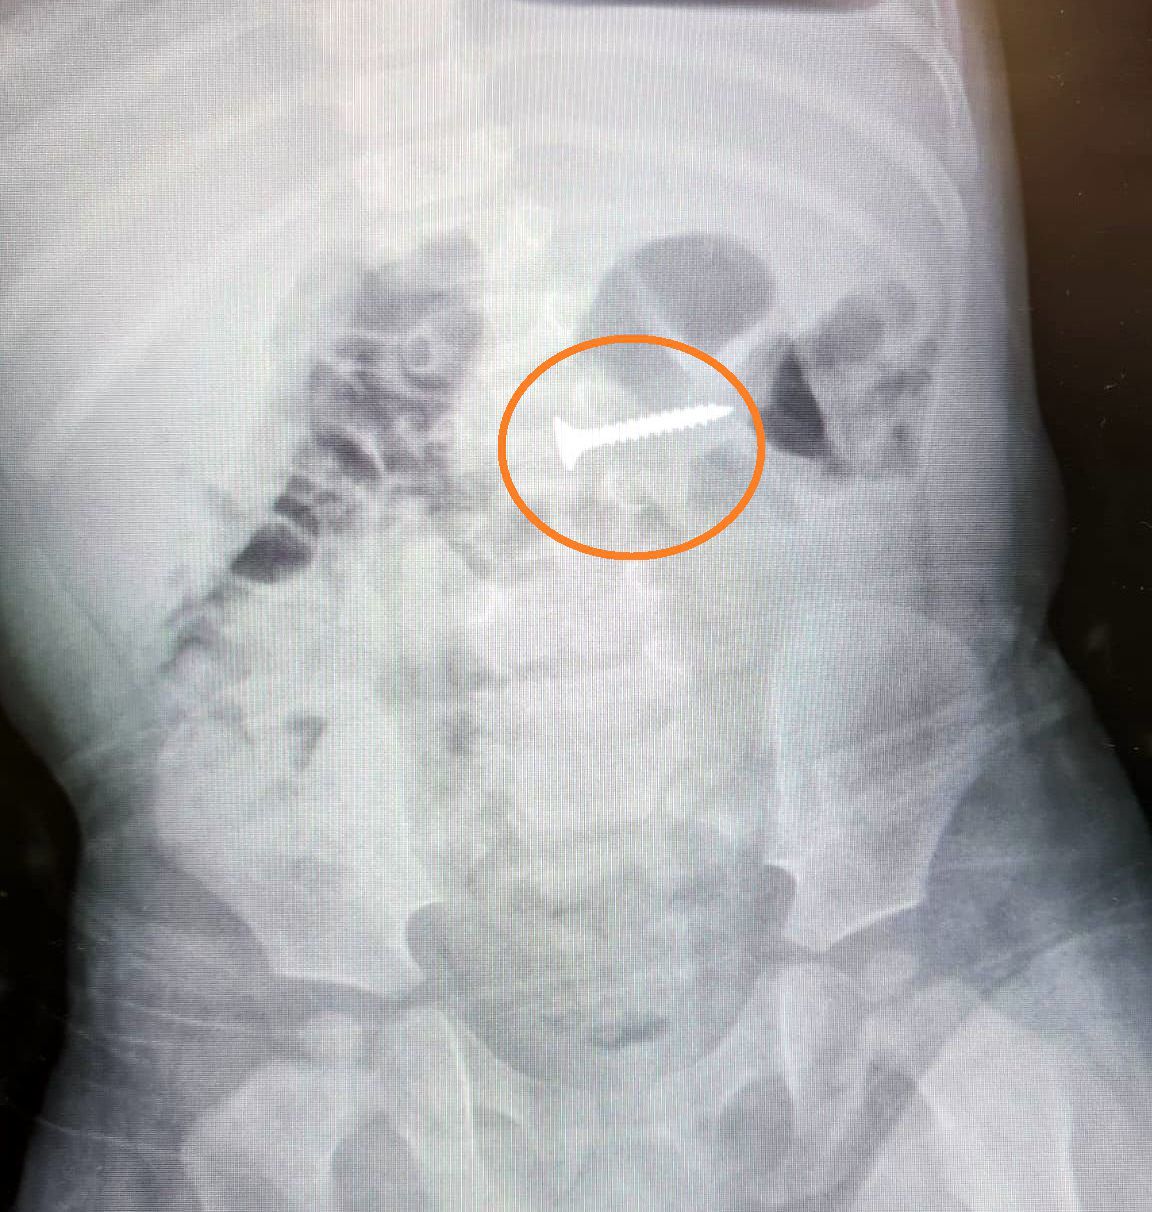

פעוט כבן שנה בלע בורג בביתו, אימו מהרה לקחת אותו למיון שם הוציאו את הבורג בשלמותו רגע לפני שהגיע לתריסריון וסיכן את חייו